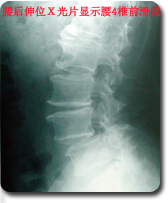

采用国际领先微创手术技术--后路内窥镜(METRx)行腰椎间盘摘除,椎管减压,并采用经皮椎弓根螺钉系统(Sextant)行复位和内固定。治疗腰椎间盘突出,椎管狭窄以及腰椎不稳等疾病。 优点:本手术采用Sextant系统通过小的皮肤切口直接放置腰椎椎弓根螺钉系统,经皮复位内固定,同时结合腰椎间盘镜(METRx)通过一个小切口(1.8cm)完成腰椎管减压,椎间植骨和融合器植入,本手术方式将Sextant技术与METRx技术相结合,以达到微创腰椎管减压、复位、融合和内固定。 |